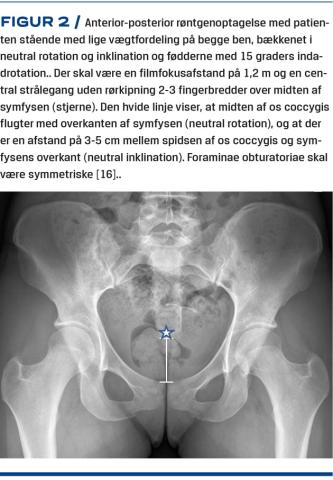

Der er et utal af radiologiske målinger til vurdering af hofteleddets morfologi, og der er dårlig evidens for, hvilke man bedst kan bruge til at beskrive morfologien [15]. Forfatterne til denne artikel finder, at i udredning af hofte-lyske-smerter er – ud over anamnesen og den objektive undersøgelse – et standardiseret røntgenbillede af hele bækkenet taget med patienten stående nøglen til at identificere de relevante hofte-/bækkenpatologier (Figur 2), nemlig hofteledsartrose, hoftedysplasi, acetabulærretroversion og pincermorfologi samt i en del tilfælde camforandringer [16].